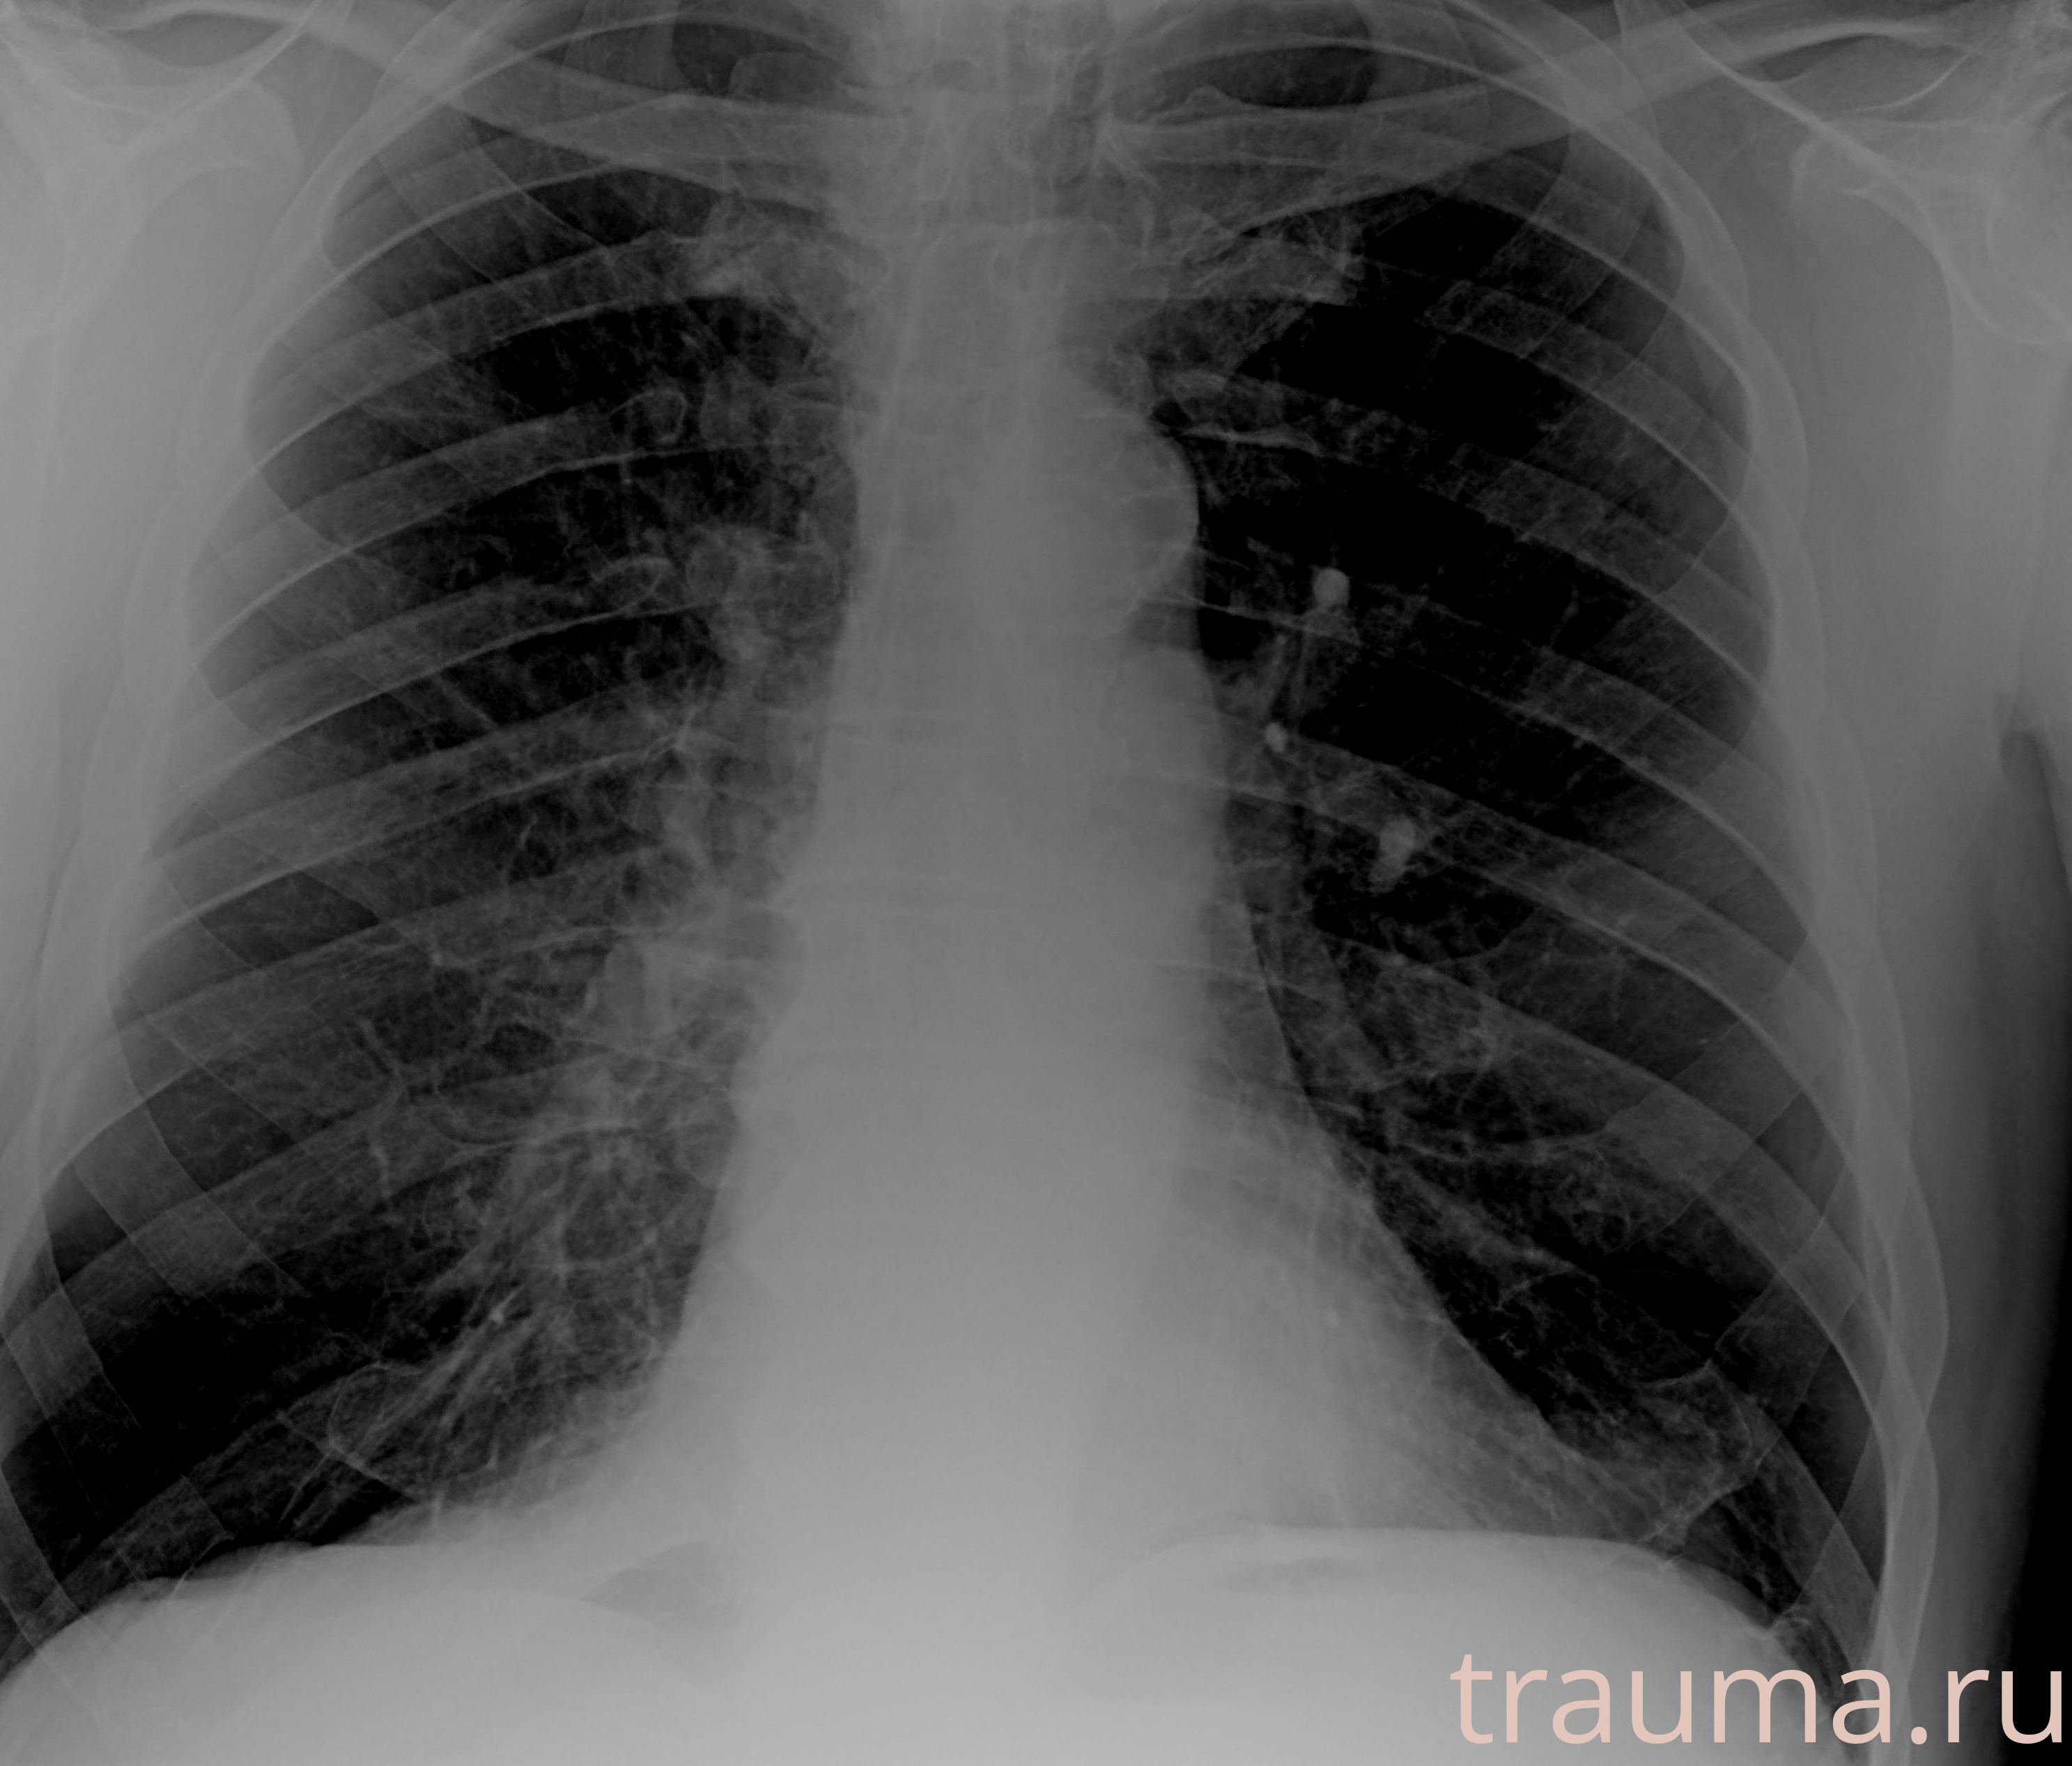

Рентгенограммы

Рентген на дому: по вашему адресу приезжает врач-рентгенолог, травматолог-ортопед с мобильным рентгеновским аппаратом, проводит диагностику травмы или заболевания, делает необходимые рентгенограммы, дает рекомендации по дальнейшему лечению. Получить качественные снимки в домашних условиях возможно благодаря уникальной методике, разработанной МосРентген Центром для института  Склифосовского

Яркость: 1   Контраст: 1   Инвертировать: 0 Увеличение: 1

Перетаскивайте мышь вверх/вниз для контраста, влево/право для яркости. Прокрутка колесом изменяет масштаб. Нажмите Сбросить для возврата к исходному изображению. При увеличении держите мышь в той области, которую хотите рассмотреть.